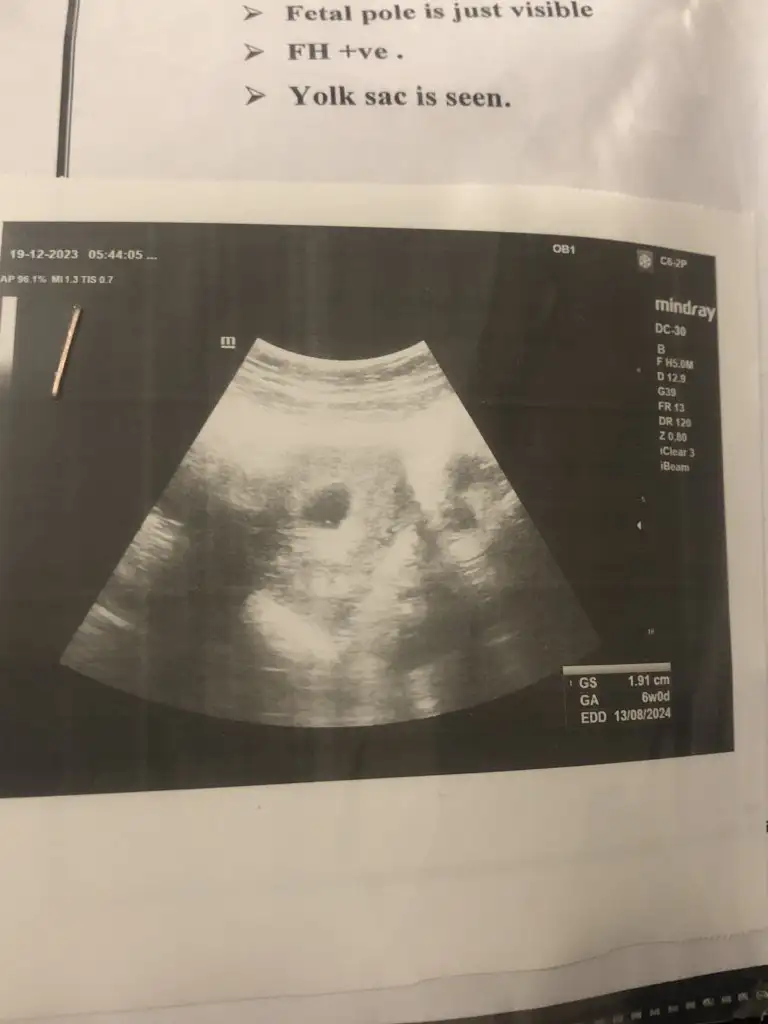

Kese uzunsa erkek yuvarlaksa kız mi ?

Kızlar bı arkadaş keseye göre tahmin yapıyor ve hep tutuyormuş iki oğlunu da bu şekilde cok yeniyken bile tahmin etmiş...ogullarinda kesesi hep uzunmuş muz gibi...yuvarlak ve yuvarlağa yakın olanlar hep kızdır diyor..ve bayağı emin konusuyor..benimki şişman bı fasulye gibi oo kesin kız görürsün dedi...sizlerin keselerinin şekli nasıldı ve cinsiyet neydi konusalimmi 😊